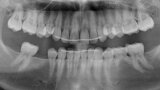

Řízená implantologie za použití řešení Planmeca all-in-one